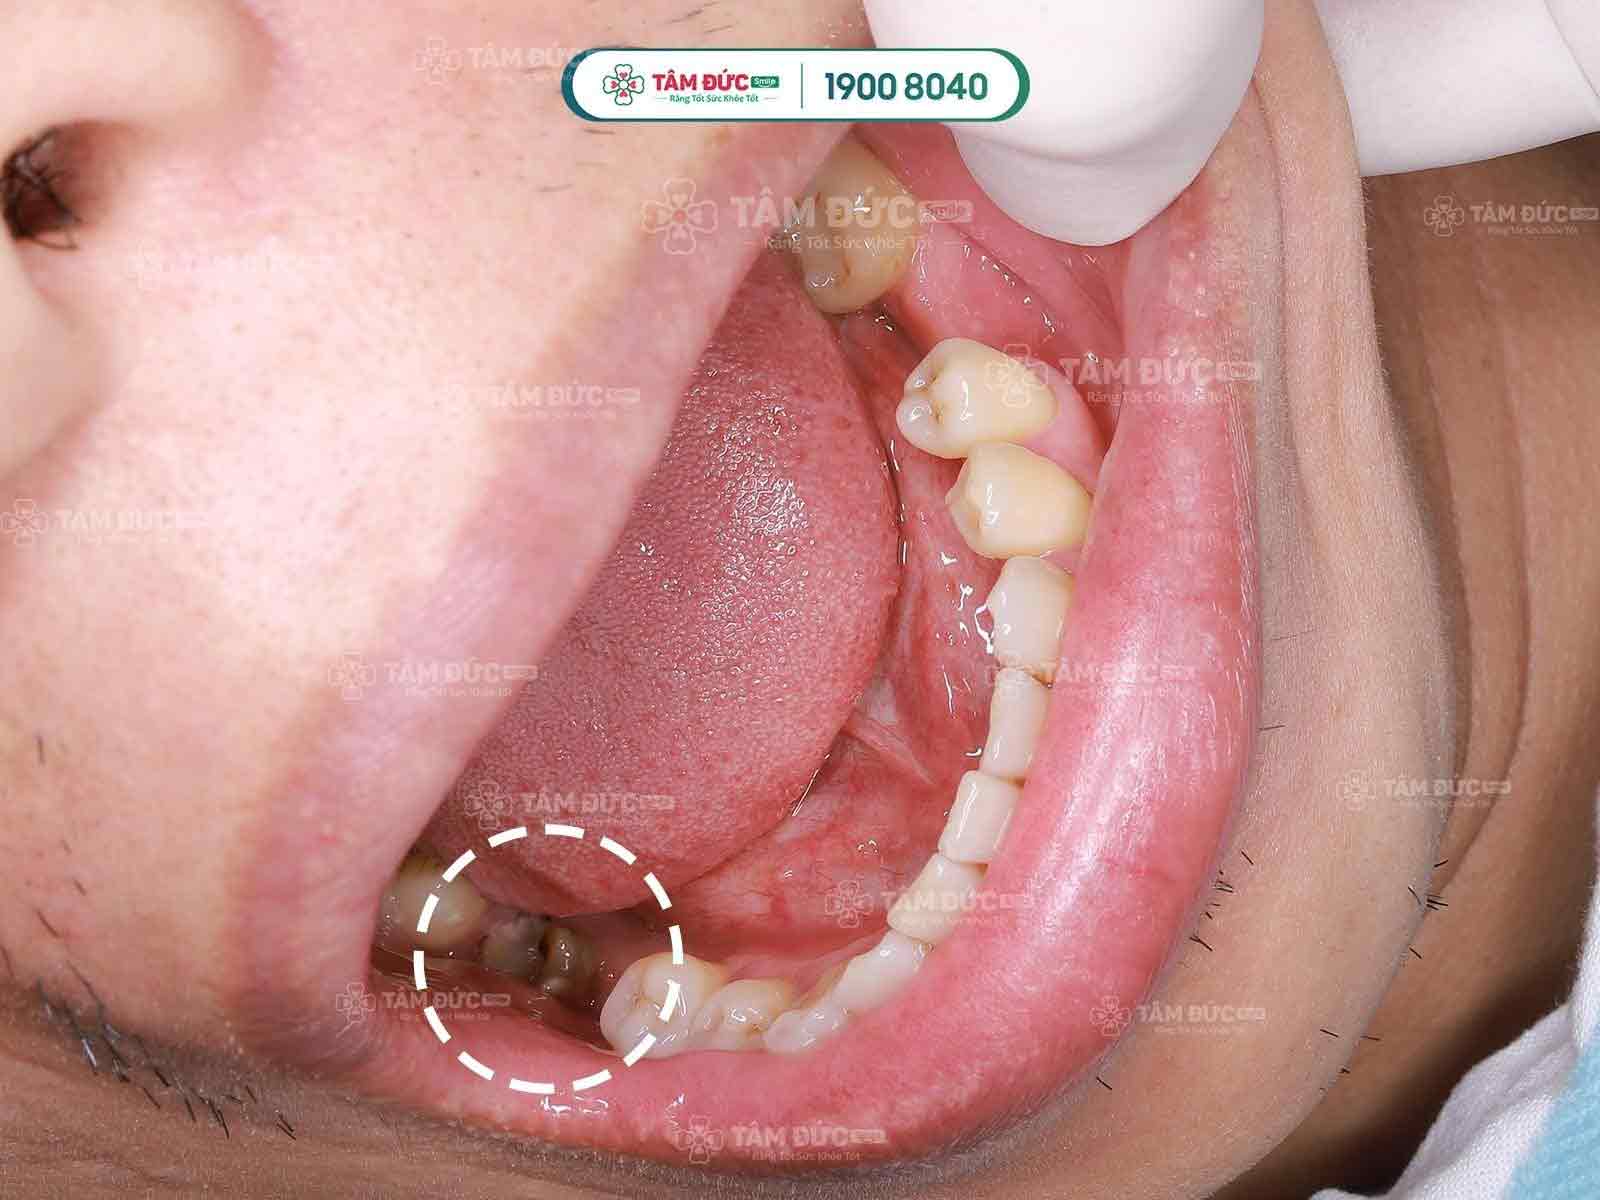

Tủy bị viêm, hư hỏng… nếu không được chữa trị tủy răng sẽ dẫn đến nhiều mối nguy hại:

- Đau nhức vùng răng bị viêm, sâu tủy.

- Ê buốt răng khi ăn, uống.

- Viêm nhiễm lan rộng, tạo mủ ở chóp răng, hình thành apxe.

- Cấu trúc xương hàm bị phá hủy nếu viêm nhiễm kéo dài, dẫn đến rụng răng.

Tủy bị viêm, hư hỏng dẫn đến nhiều mối nguy hại